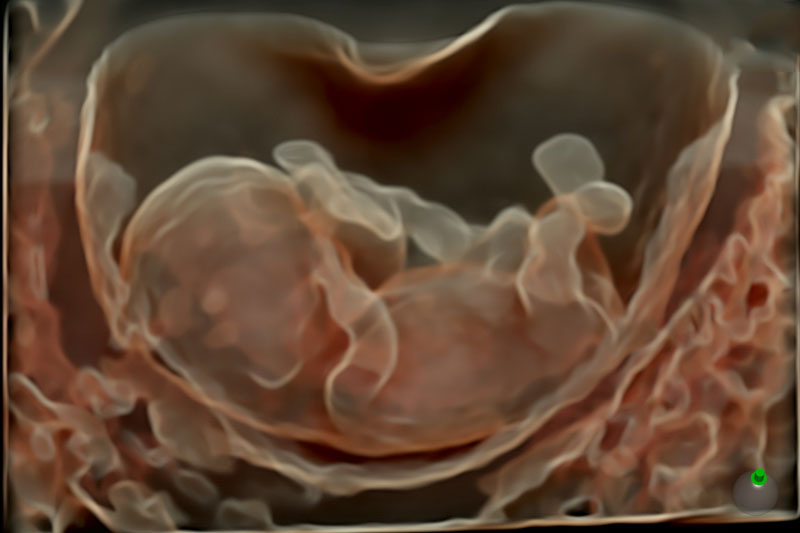

Dr. Ashwini Rathi (MD, MRCOG) is a leading Fetal Medicine Specialist and the Director of Mumbai Fetal Medicine Centre—Mumbai’s first stand-alone dedicated fetal medicine facility. With over 13 years of experience, she is recognized for her precision-driven approach, advanced diagnostic skills, and compassionate care for expectant mothers and their babies.

Dr. Ashwini Rathi offers world-class fetal medicine services with a unique blend of clinical expertise, advanced technology, and compassionate patient care to ensure the safest outcomes for both mother and baby.

FMF-certified scanning protocols, high-resolution ultrasound, and global screening standards.